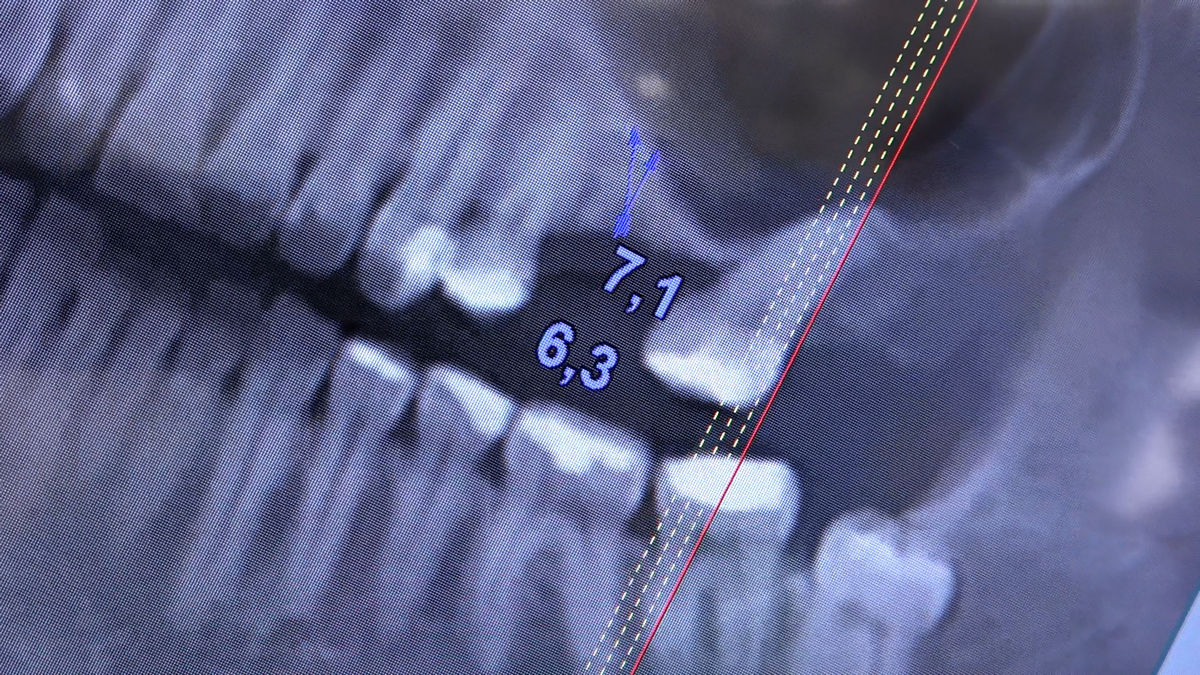

Chirurgia implantologiczna to temat wiodący 5 Sesji X Sezonu Practiculum Implantologii, która się odbyła 23-24 października 2020 roku. Bierze w nim udział 16 adeptów implantologii stomatologicznej. Zabiegi z udziałem Pacjentów jak zwykle poprzedziło omówienie i planowanie, tym bardziej, że zgodnie z planem wykonana została implantacja z wykorzystaniem szablonu chirurgicznego, który przygotowało laboratorium dentystyczne Wiligała Lab. Kursanci wykonywali szereg zabiegów implantologicznych i chirurgicznych oraz regeneracyjnych z zastosowaniem PRF, w tym sinus lift. Przeprowadzali je pod kierunkiem Lidera Umiejętności Implantologicznych dr n.med. Violetty Szycik, która wysoko oceniła wykonanie zabiegów.